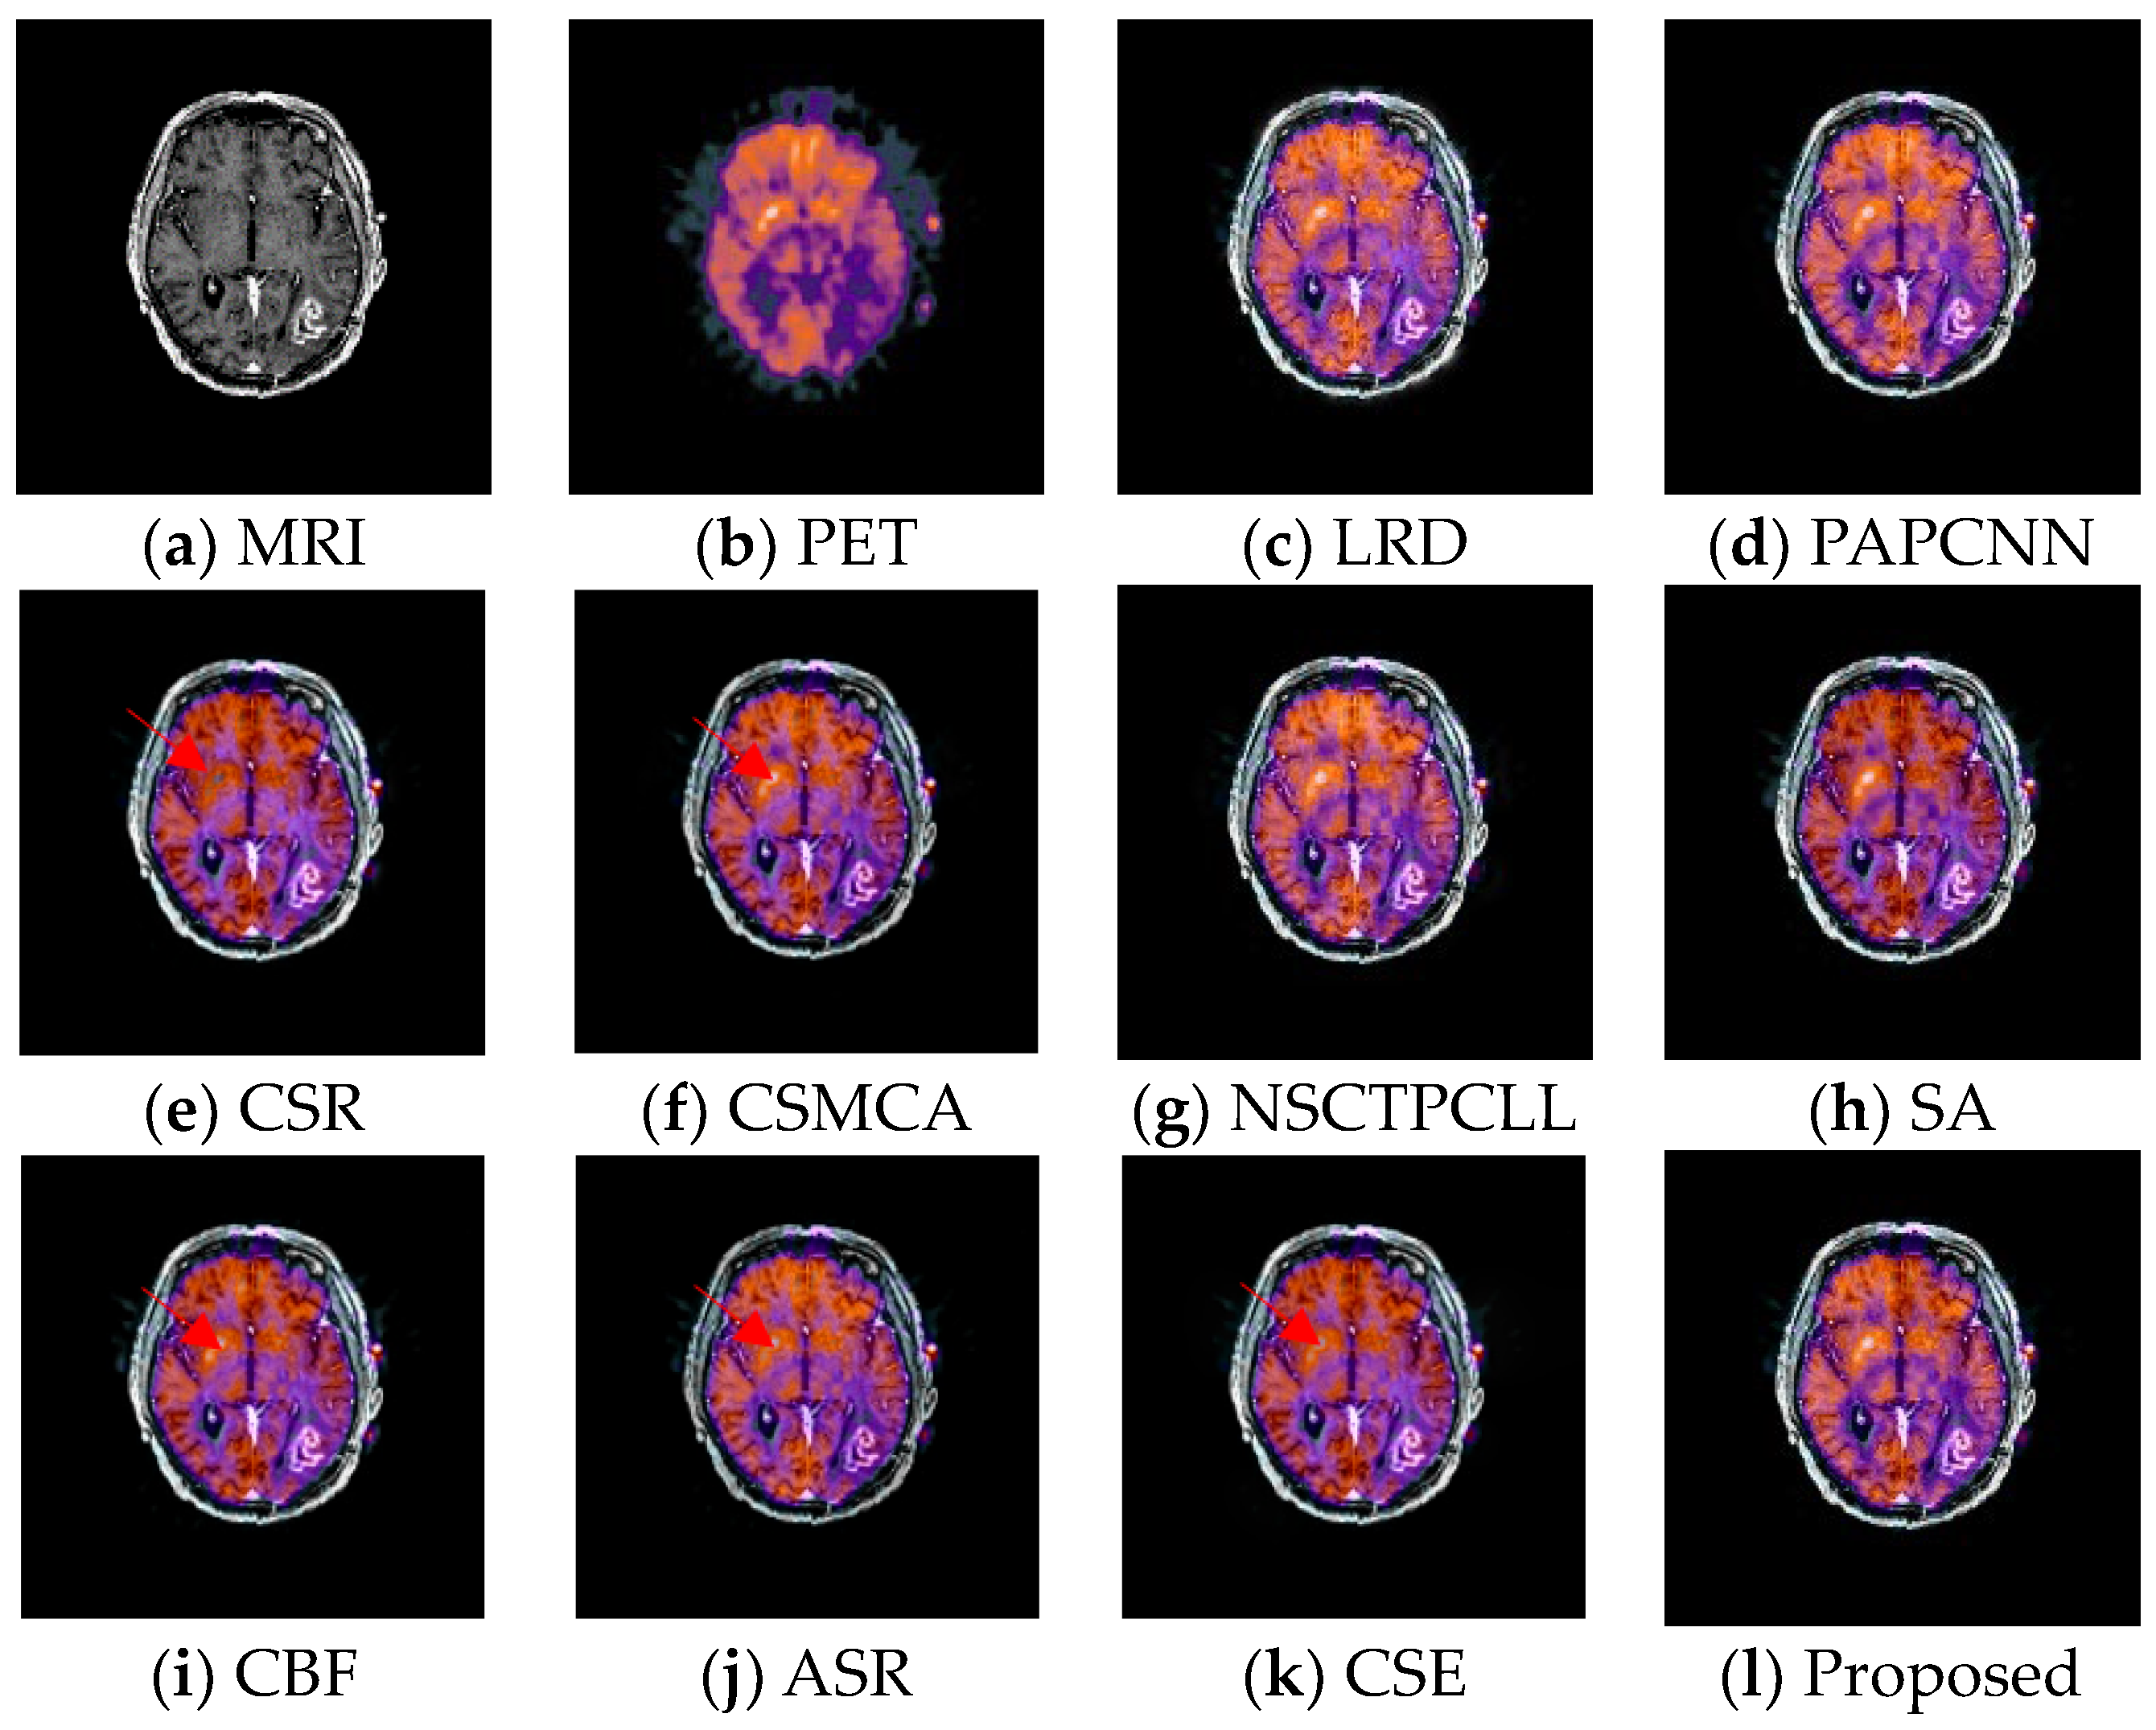

4.4. Experimental Results